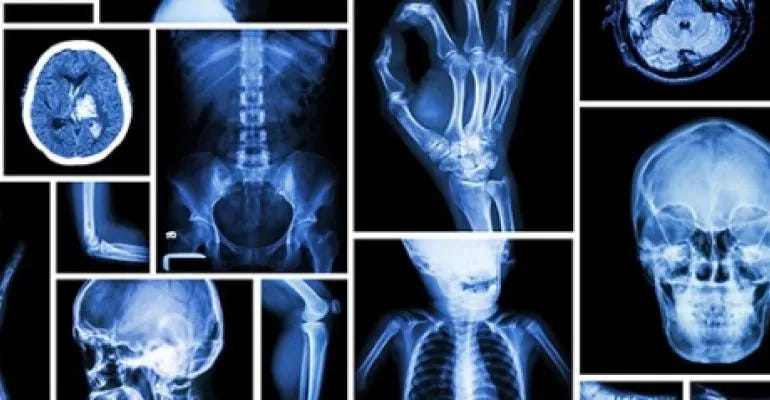

Initially, X-rays were used only to detect dense structures such as foreign bodies and stones and in evaluation of bones. With improvement in X-ray equipment, soft tissues such as breast began to be imaged using X-rays. Thus, mammography originated which is now an indispensable tool in screening for breast cancer.

In the second half of the 20th century, particularly in the last three decades, there has been a paradigm shift in the practice of radiology with the advent of Ultrasound, Computed Tomography (CT) and Magnetic Resonance Imaging (MRI) in clinical practice.

The CT scan also came into clinical use during the 1970s in the UK. It was initially dedicated to head imaging only but with improvements in technology, imaging services for “whole body systems” became available. The CT scan uses X rays to create cross-sectional images of the body. One of the chief advantages of CT scan is its speed with the new generation scanners imaging large body parts in just few seconds.

Magnetic Resonance Imaging (MRI) came into wide clinical use in the 1980s. It is an advanced medical imaging modality with excellent resolution of different structures in the body and does not use potentially harmful ionising radiation.